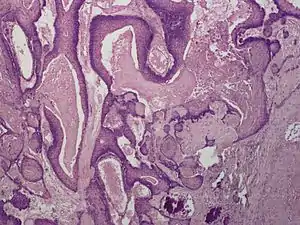

Proliferating trichilemmal cysts (also known as a "Pilar tumor", "Proliferating follicular cystic neoplasm", "Proliferating pilar tumor", and "Proliferating trichilemmal tumor"[2]) are a cutaneous condition characterized by proliferations of squamous cells forming scroll-like structures.[2][3]:678